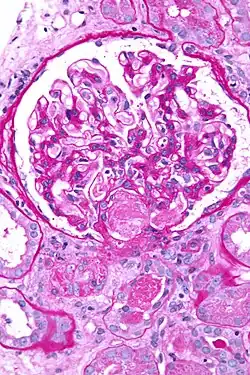

![]() Imagen del glomérulo (en rojo) dentro de la cápsula de Bowman. | ||